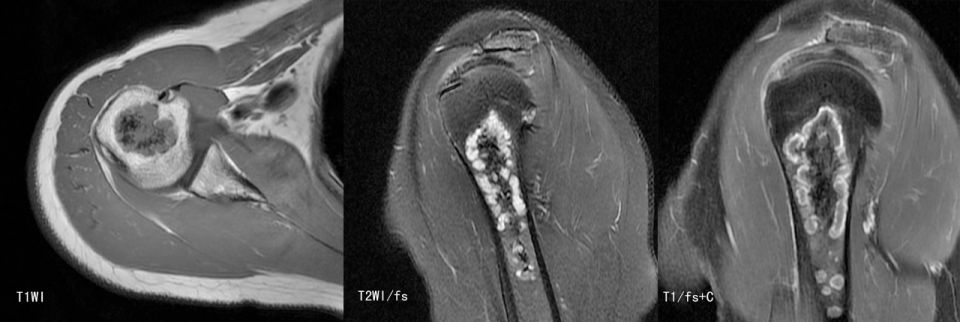

瘤软骨为肿瘤细胞产生的软骨基质,多来源于软骨类肿瘤,或内有化生瘤软骨成分的其他肿瘤如成软骨型骨肉瘤。瘤软骨为软组织密度,未钙化时,主要通过 MRI 检查显示。由于瘤软骨多由富含水分及粘多糖的透明软骨构成,故 T1WI 呈偏低信号,T2WI 或 PDWI 呈明显高信号,被低信号的纤维间隔分开呈分叶状(图 24、图 25a-b),增强扫描多呈不均匀分隔状强化(图 25c),主要是纤维间隔强化,瘤软骨强化不明显之故。

图片

图 24.瘤软骨:内生软骨瘤

图 25.瘤软骨:内生软骨瘤